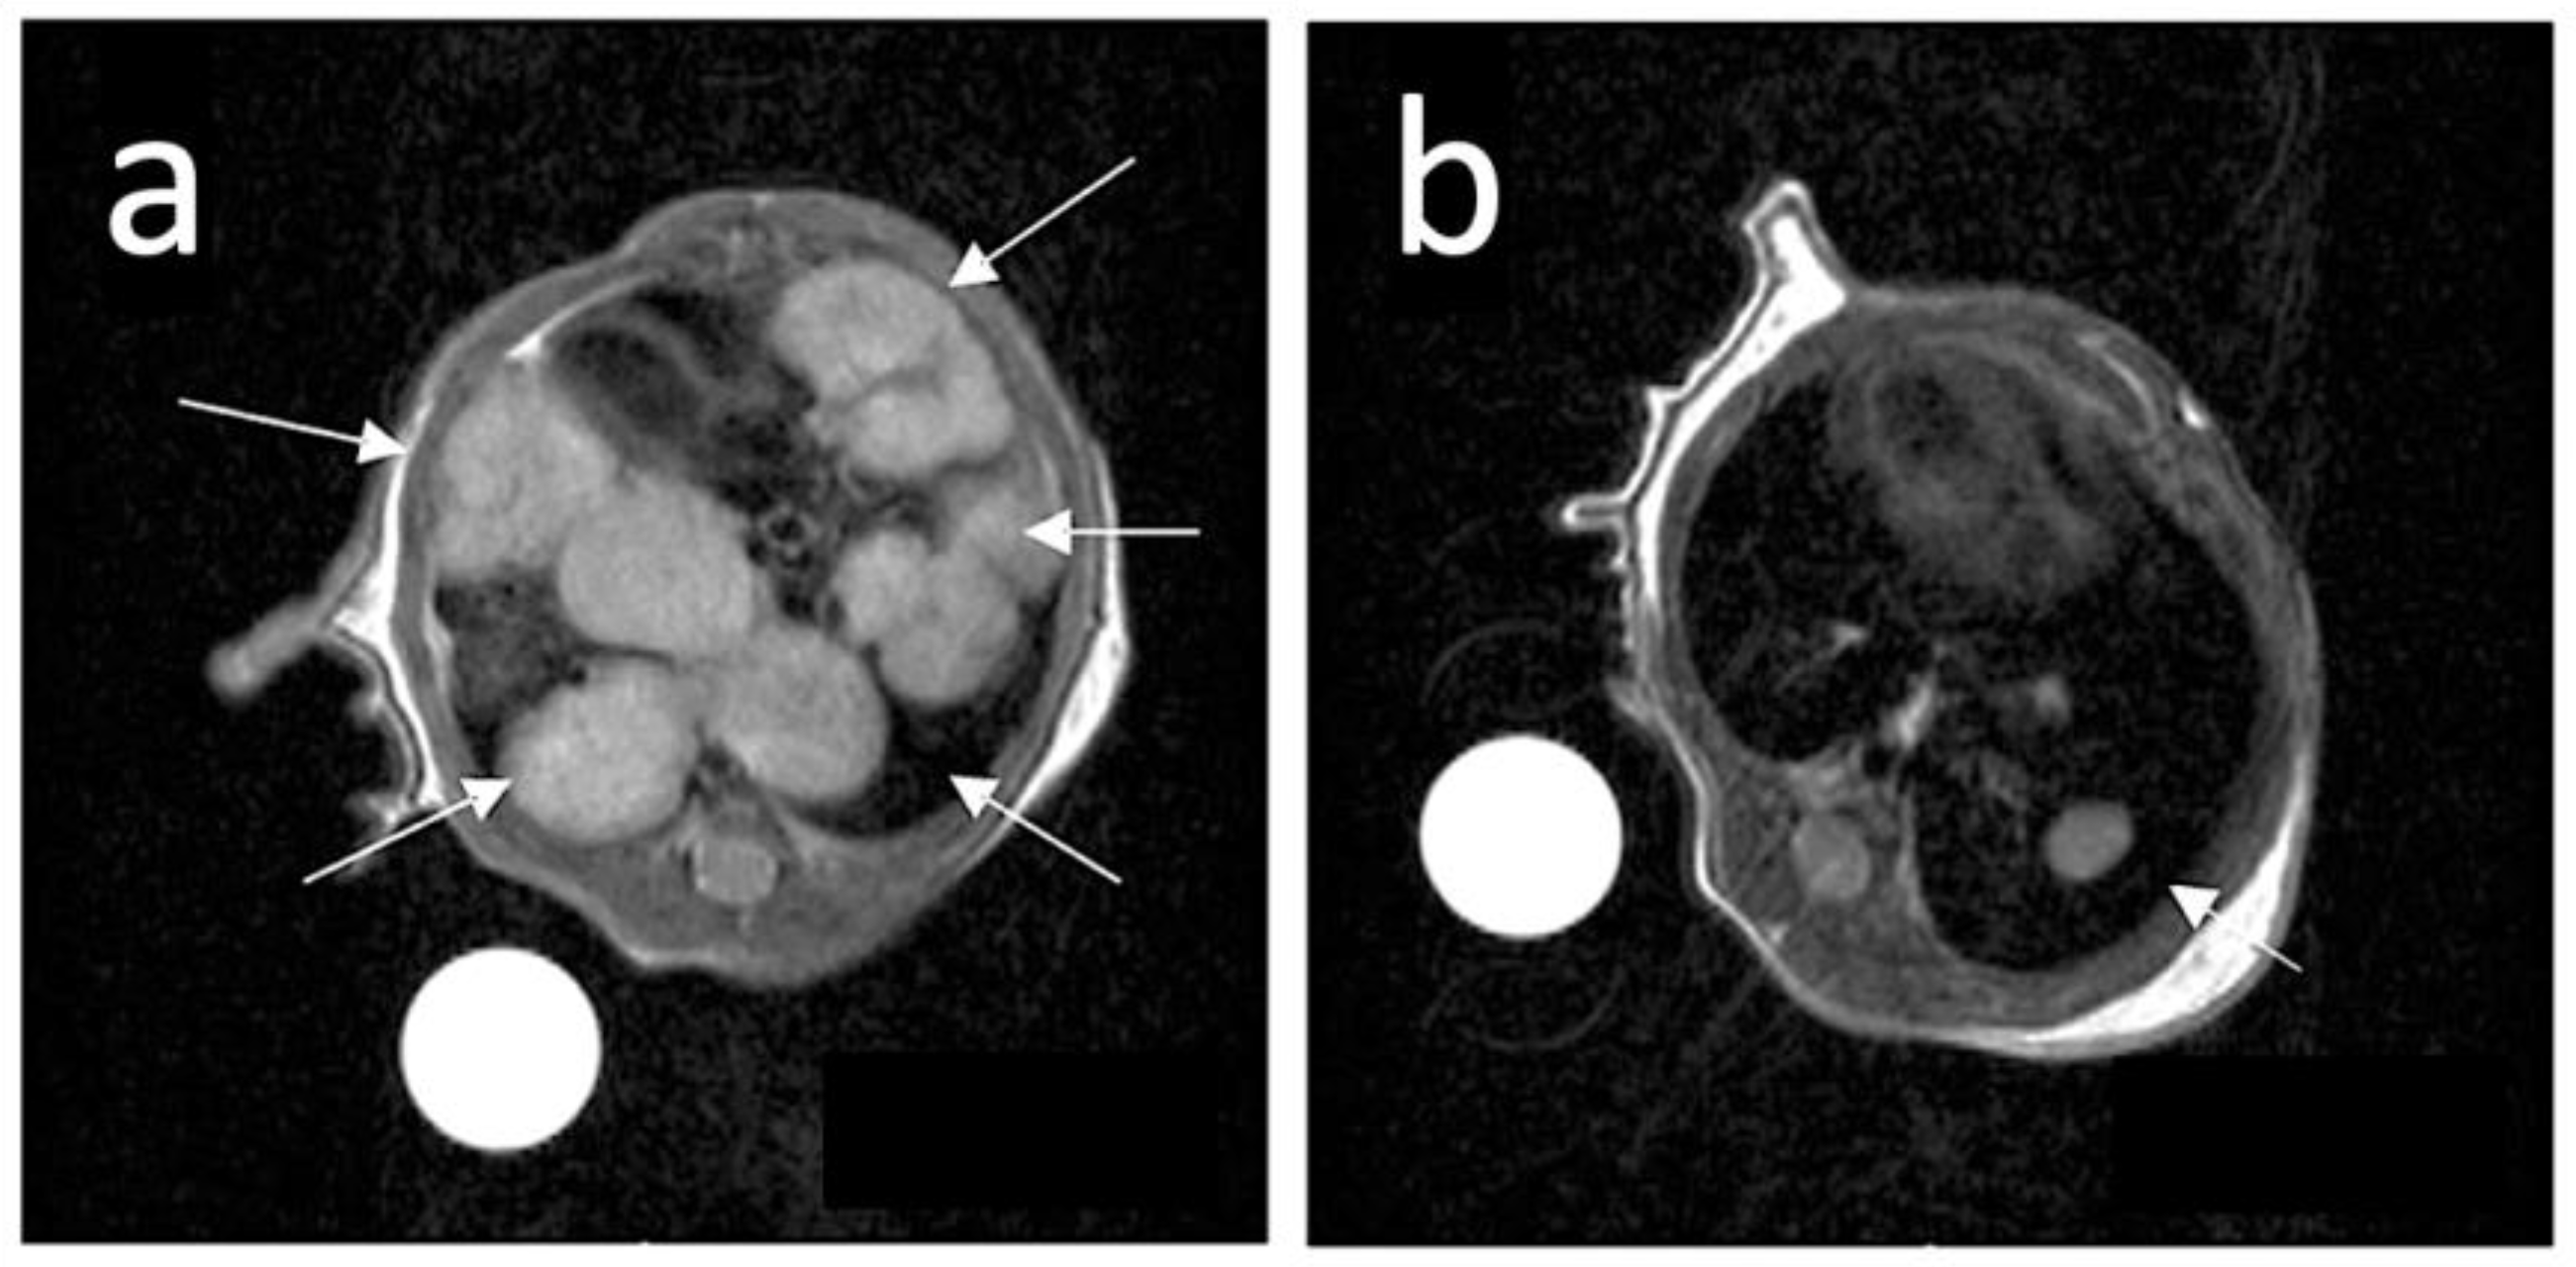

- Alberti, D.; Protti, N.; Toppino, A.; Deagostino, A.; Lanzardo, S.; Bortolussi, S.; Altieri, S.; Voena, C.; Chiarle, R.; Geninatti Crich, S.; et al. A Theranostic Approach Based on the Use of a Dual Boron/Gd Agent to Improve the Efficacy of Boron Neutron Capture Therapy in the Lung Cancer Treatment. Nanomedicine 2015, 11, 741–750. [Google Scholar] [CrossRef]